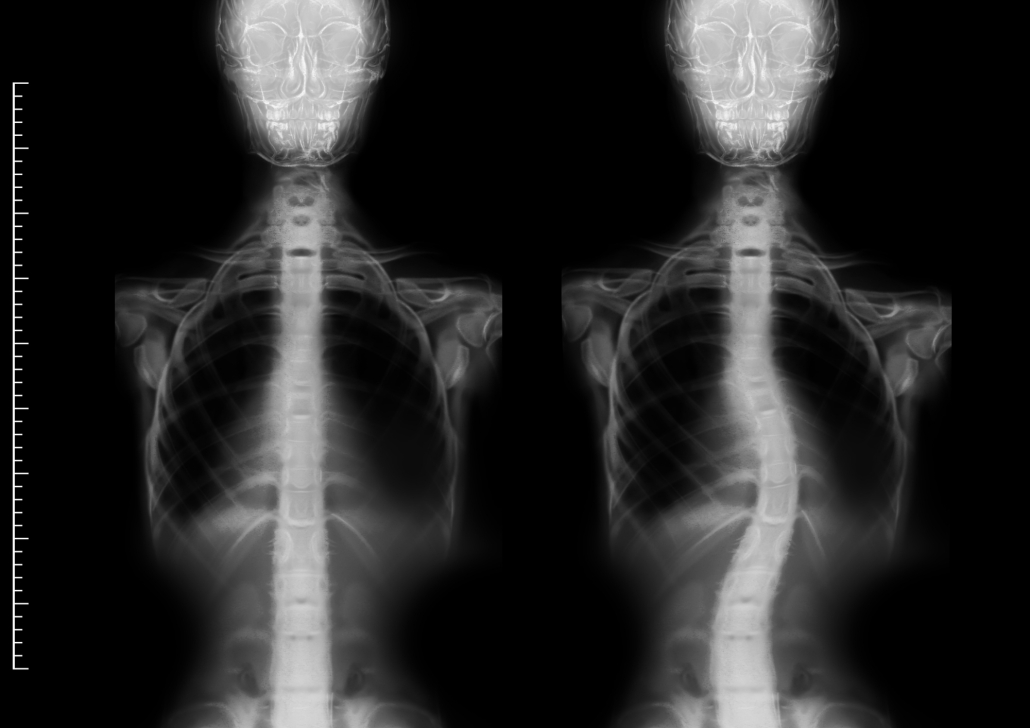

- Skolyoz (Yana Doğru Eğrilik): Omurganın sağa veya sola doğru “C” ya da “S” harfi şeklinde eğilmesidir. Sadece yana yatma değil, omurganın kendi ekseni etrafında dönmesi (rotasyon) de söz konusudur. En sık ergenlik döneminde görülür (Adolesan İdiyopatik Skolyoz).

Omurga eğriliği, erken fark edildiğinde yönetilebilir bir süreçtir. “Eğrilik” kelimesi sizi korkutmasın. Çocuğunuzun veya kendinizin omurgasında bir asimetri fark ederseniz, bir omurga cerrahisi uzmanına başvurarak çekilecek basit bir tüm omurga röntgeni (Skolyoz grafisi) ile durumu netleştirebilirsiniz. Unutmayın, en iyi tedavi erken teşhistir.